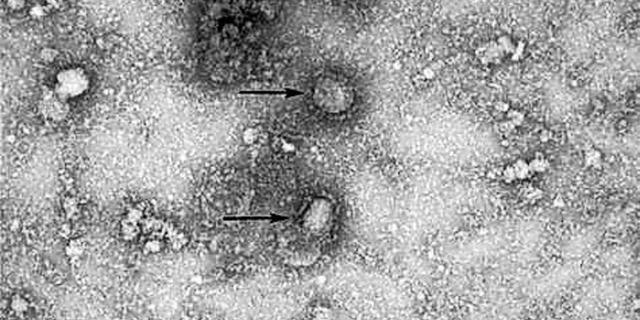

新冠病毒直径只有60-140纳米,一般细胞的直径在10-20微米,而头发丝的直径在60-90微米。

病毒由外层的蛋白外壳和核酸组成,它没有细胞器。

但是,因为病毒太小,我们的技术限制了我们对其进行更细致全面的研究,所以要想鉴别出某种病毒,带来很大困难。